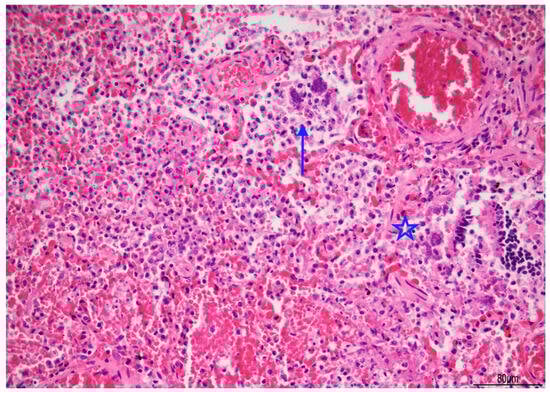

Lung histology revealed acute exudative pneumonia with abundant neutrophils, fibrin deposition, intra-alveolar hemorrhage, bacterial colonies (cocci), abundant lipid-laden macrophages (compatible with early lipoid pneumonia), and focal foreign-body giant cell reaction to aspirated material (Figure 7, Figure 8 and Figure 9). Histochemistry for PAS, PAS-D, and Grocott were performed to rule out fungal colonization and resulted negative.

Figure 7. Acute pneumonia: alveoli were filled with neutrophils and bacteria (blue arrow). Bacteria were also found in bronchioles (star). Abundant erythrocytes within the alveoli were also present (Hematoxylin and Eosin, 20 HPF).